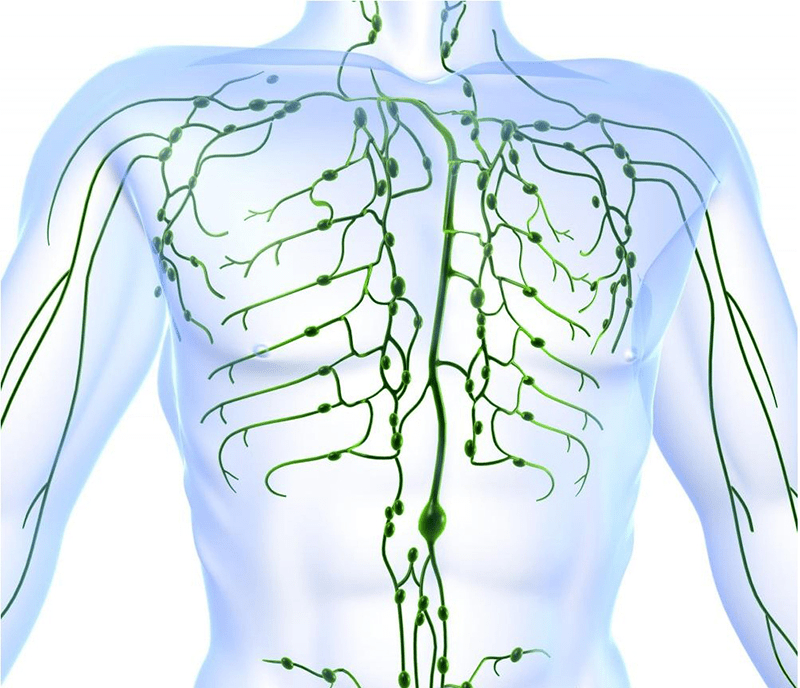

Why Your Lymphatic System Is Crying Out for Help – And Goosegrass Answers the Call

Picture this: Sarah, a 42-year-old marketing executive and mom of two in Austin, Texas, woke up every morning with swollen fingers that made typing painful. “I felt like my body was holding onto every toxin from stress and processed food,” she shared. Within two weeks of adding goosegrass tea to her morning routine, the puffiness melted away. “My rings fit again, and I had this unexpected surge of energy—like my body finally unclogged itself.”

Research suggests goosegrass acts as a powerful lymphatic tonic. A 2020 study published in Molecules highlighted its ability to stimulate immune cell activity, supporting the movement of lymph fluid that carries away waste. Traditionally used to reduce swelling in lymph nodes, it may help with conditions like mild lymphedema by promoting natural drainage.

Rate your own lymphatic “heaviness” on a scale of 1-10 right now. If it’s above 5, this could be game-changing. But how does it tackle the bigger detox picture? Keep reading—the foundation is just getting laid.

Free radicals? Daily stressors? Goosegrass contains natural antioxidants and immunomodulatory compounds. A 2020 study showed its extracts significantly stimulated lymphocyte activity—key players in your body’s defense.